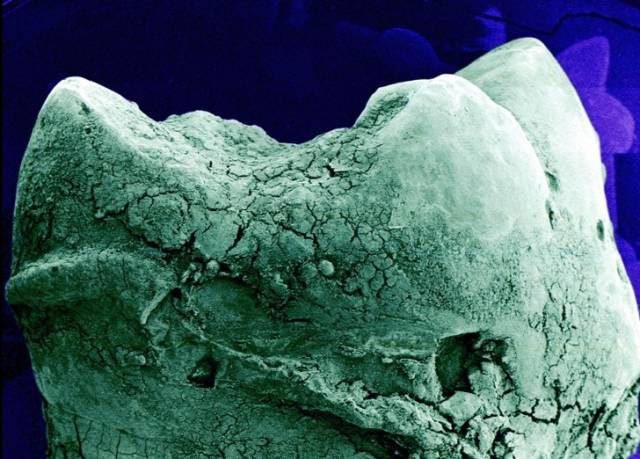

Кость